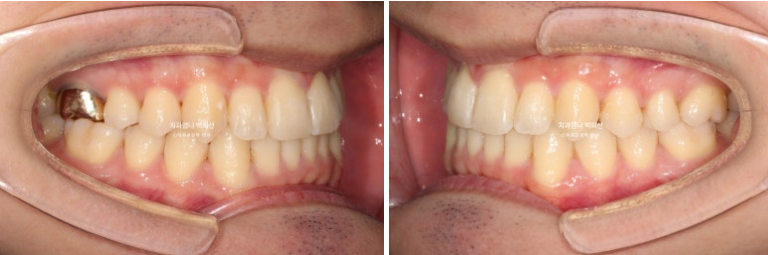

22.10~25.03

뻗쳐있던 앞니와 송곳니가 개선이 되고 스마일라인이 정돈되었습니다.

앞니 기울기와 중심선이 개선이 되니 비대칭처럼 보이던 것도 해소가 되었습니다.

앞니뻗침이 개선되었습니다.

앞니 뻗침과 돌출이 위 아래 각각 2mm 가량 개선된 것이 보입니다.